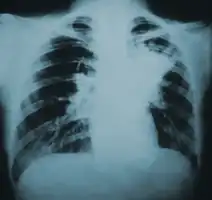

Chest X-ray

Blastomycosis is primarily a lung infection in about 70% of cases.[14] The onset is relatively slow and symptoms are suggestive of pneumonia, often leading to initial treatment with antibacterials. Occasionally, if a lesion is seen on X-ray in a cigarette smoker, the disease may be misdiagnosed as carcinoma, leading to swift excision of the pulmonary lobe involved. Upper lung lobes are involved somewhat more frequently than lower lobes.[14] If untreated, many cases progress over a period of months to years to become disseminated blastomycosis. In these cases, the large Blastomyces yeast cells translocate from the lungs and are trapped in capillary beds elsewhere in the body, where they cause lesions. The skin is the most common organ affected, being the site of lesions in approximately 60% of cases.[14] The signature image of blastomycosis in textbooks is the indolent, verrucous or ulcerated dermal lesion seen in disseminated disease. Osteomyelitis is also common (12–60% of cases). Other recurring sites of dissemination are the genitourinary tract (kidney, prostate, epididymis; collectively ca. 25% of cases) and the brain (3–10% of cases).[14]